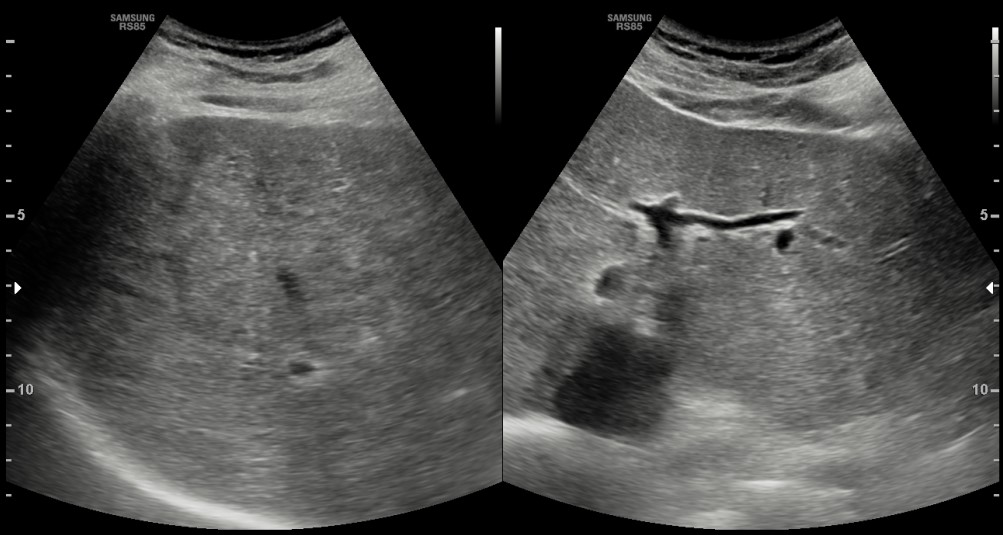

[366,Hepatobiliary [HB]] 62/M,Abnormal finding on upper abdominal ultrasonography during a health check-up

Hepatobiliary [HB]

US,

What is the most likely diagnosis?